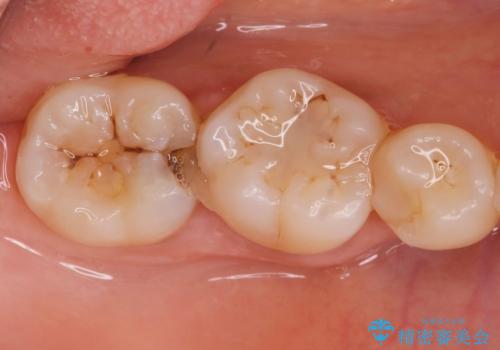

歯に食べ物が詰まる。

- 歯に食べ物が詰まるとの事で来院。

虫歯により歯が欠けていたので拡大鏡下で虫歯を除去した後、セラミックの詰め物で治療しました。